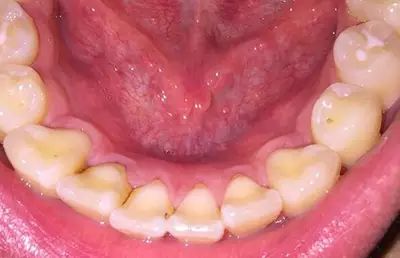

由于长期口腔卫生条件不佳,大量细菌、色素沉积在牙齿上,尤其是根部,形成牙结石刺激牙龈,这种牙结石呈黄色或者黑色,刷牙很难刷掉,可通过洗牙去除。

当龋齿已经是深龋或者是中龋的时候,蛀洞相对比较深,非常容易进行分辨。牙体的组织受到细菌侵蚀之后形成一定的龋洞,而由于洞内的大量黑褐色腐质的存在,龋洞的周围受到感染的牙体组织也呈现黑褐色。